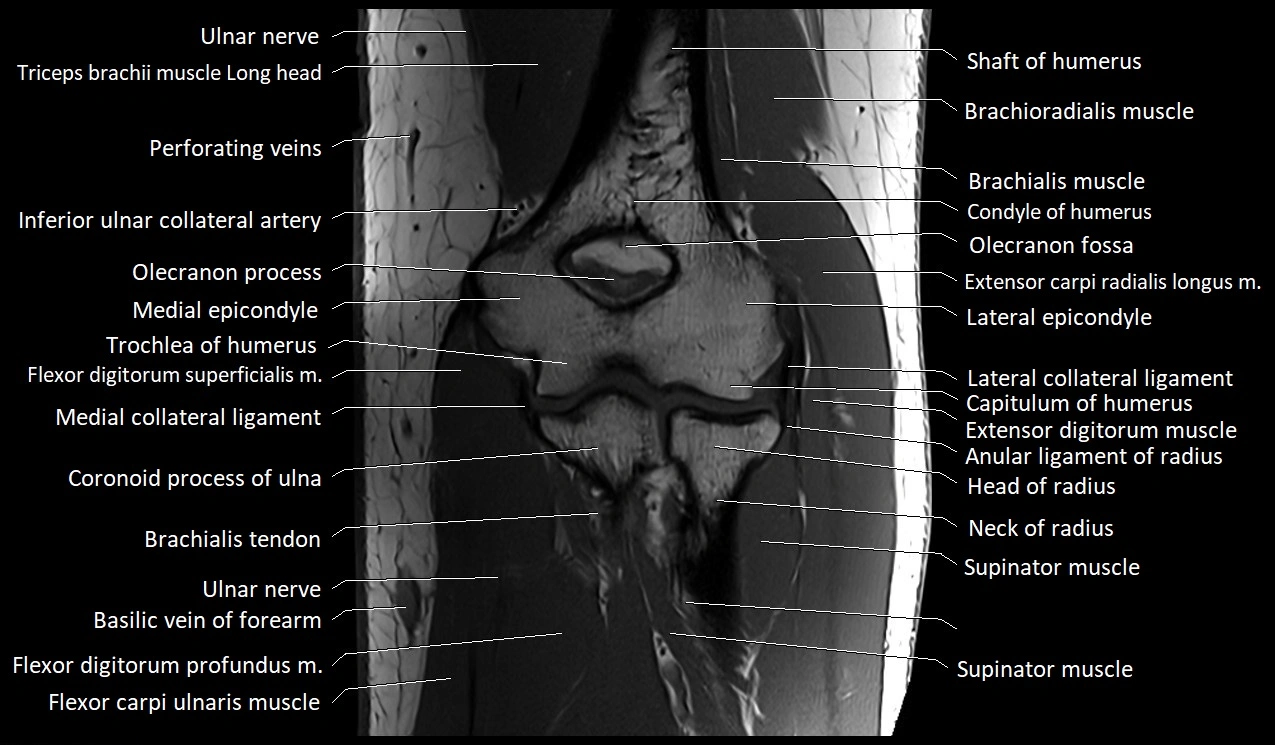

MRI image

image